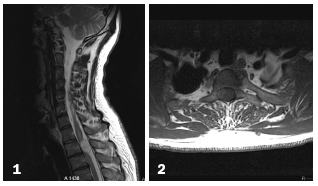

A 40-year-old man presented with episodic cervical pain radiating to the left shoulder. MRI scans show a well-marginated nodular lesion in the intradural extramedullar space at the T2 level (1), with a broad contact surface between the lesion and the posterior and left lateral wall of the upper thoracic spinal canal. The spinal canal is largely occupied by the lesion, causing the cord to be severely compressed and displaced to the right (2).